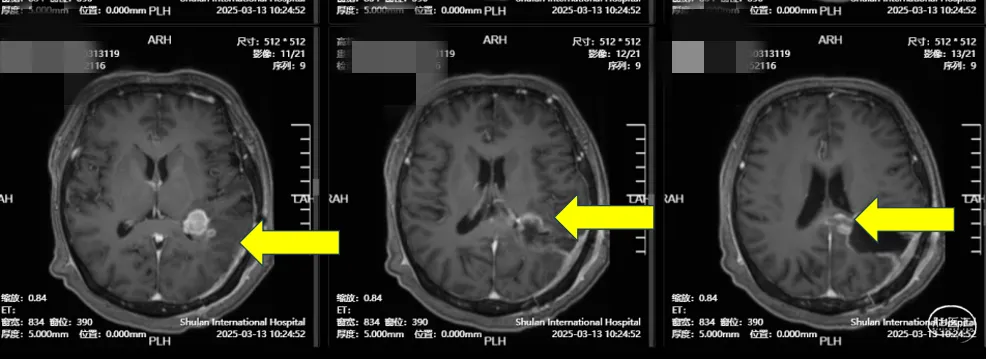

“胶质母细胞瘤”作为一种极其恶性、生长迅速的脑肿瘤,术后的治疗方案对于患者来说至关重要。术后,高女士家属得知树兰(济南)医院神经肿瘤科陶荣杰教授团队在神经肿瘤领域的治疗具有丰富的经验,随即慕名前往。复查影像结果显示:术后肿瘤仍有残留。

![]()

(图3、图4:术后1月:肿瘤残留)